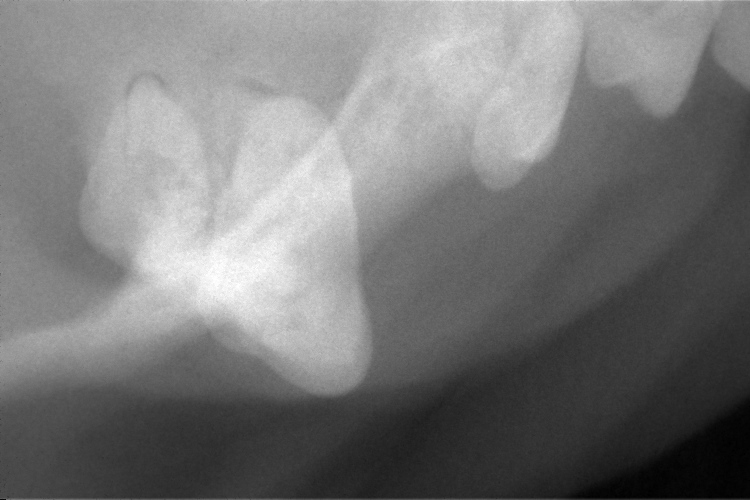

歯肉の発赤があった右上顎第4前臼歯です。

歯根部の異常は確認されませんでした。